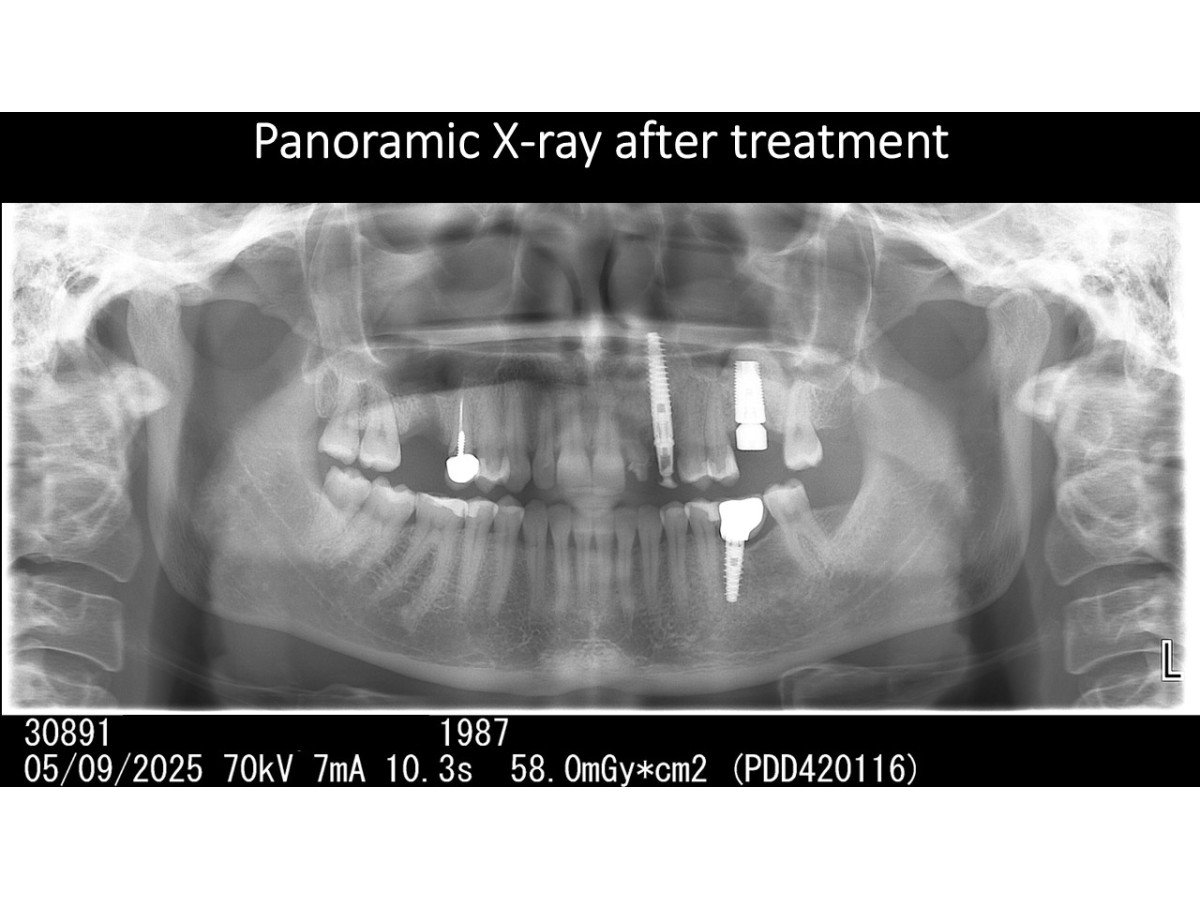

Tooth extraction, direct implantation with immediate loading, bone augmentation, crestal sinus lifting

Clinical case:Removal of an impacted tooth, direct implantation with immediate loading, bone augmentation, crestal sinus lifting, soft tissue monitoring